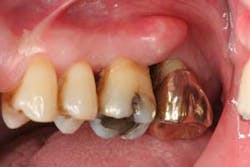

Figure 4: Example of the type of splint used in the areas to be surgerized.

After explaining treatment options, a plan that was focused on saving as many teeth as possible was fabricated. This included four quadrants of scaling and root planing, splinting the areas of severe bone loss (figure 4), osseous surgery with hard- and soft-tissue regeneration, extracting tooth No. 15 (complete bone loss to the apical extent of the root), and diligent maintenance intervals.